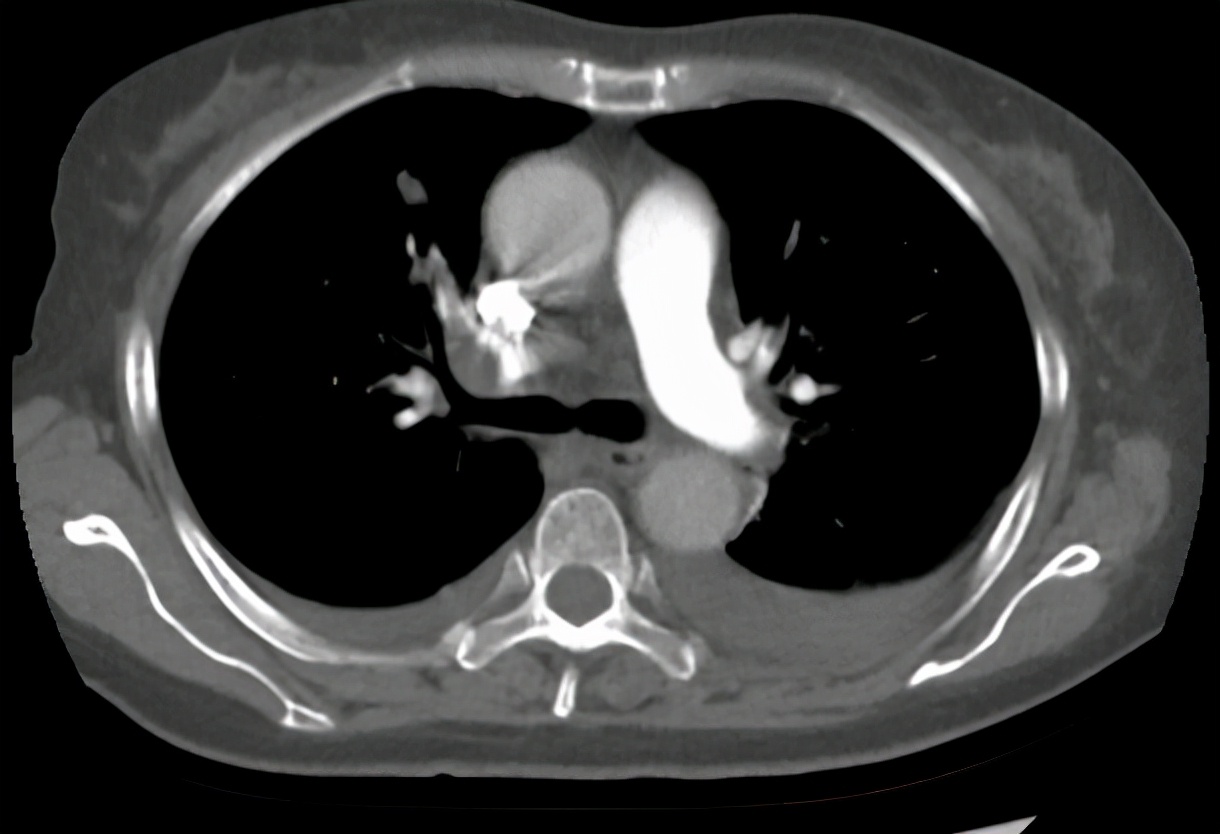

2020-12-23肺动脉CTA

放疗结束后3个月,患者出现胸闷气促,氧饱和度下降,至我科再次就诊,2020-12-23肺动脉CTA:双肺肺动脉多发栓塞。双肺炎症考虑;附见:双侧胸腔积液。考虑患者疾病进展,出现胸腔积液,肺栓塞严重威胁生命,予吸氧、抗凝、化痰、抗感染、营养支持治疗。期间腹胀明显,腹围较前也增大了,肝功能及胆红素进一步升高,考虑有腹水及胆道梗阻可能, 2021-1-6 全腹部CT:胰腺恶性肿瘤化疗后改变,肝脏第二肝门区占位,网膜多发结节灶,考虑转移瘤,建议随诊增强复查。低位性胆道梗阻伴肝内、外胆管明显扩张,胆囊内胆汁淤积。大量腹盆腔积液。予腹腔穿刺引流、护肝、降胆红素治疗,效果不佳,患者精神越来越差,患者想要回家见亲戚朋友最后一面,选择自动出院。